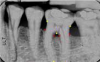

All radiographs used in this study were taken and processed using conventional, film-based standard equipment. All radiographs selected for the study were then scanned using a flatbed scanner (Epson Expression 10000XL-Graphic Arts Scanner, Epson America Inc., Long Beach, CA, USA) to a 500 x 400 dpi resolution, 10-bit grey values and then transferred to a computer (IBM-PC, Lenovo, New York, USA) PC: 1.83 GHz. Digital manipulations were performed and measured using image analysis software for Windows (ImageJ 1.32j, National Institutes of Health). ImageJ is a public domain Java image processing program, based on NIH Image, which calculates area and pixel value statistics for user-defined selections.15 Contrast of the images was enhanced by using background subtraction tool. All radiographs were evaluated under 10-fold magnification. Anatomical landmarks, CEJ, restorative margins, alveolar crest, furcation fornix, and root apicies, were identified on the radiographs. The alveolar crest level was apical to furcation fornix in order to be included in the study. A single observer was used in this study to detect the radiographic landmarks. The observer’s measurements were repeated and averaged to help avoid study errors, promote consistent uniformity and maximize the sensitivity for detecting radiographic changes.16 Periapical radiographs were used to measure bone loss between the fixed reference points17,18 in percentage of the entire root length rather than millimeter measurements (Figure 1 and Figure 2).19-22 After fixed points were identified, both images were adjusted so that the angulation difference was minimized. Although this method does not provide the bone loss in absolute numbers, the technique allows for comparison of bone levels in the same tooth in sequential radiographs. The influence of methodical and elongation errors was introduced into all sample results, and errors in this technique were reported to be as small as 2%.23

Cemento-enamel junction (CEJ), alveolar crest (AC), furcation fornix (Fx), and root apex (Ax) were identified on the baseline and subsequent radiographs. Linear measurements between the fixed reference point (CEJ or restoration margin) and radiographic apex were made along the root surfaces on both mesial and distal roots using ImageJ.23 The program set the linear distance from CEJ or restoration to the radiographic apex at 100%, denoting the total root length. The linear distance between the apex and AC, as well as fornix and AC were assessed and recorded for each root. Each time a different root or radiograph was chosen the root length was re-measured and set at 100%. The same measurement was repeated on each subsequent radiographic image and recorded. The mesial and distal root surface measurements were not averaged together and were used in the calculation separately from each other. Radiographs were further reviewed to record presence or absence of an adjacent tooth. The condition of having a tooth adjacent to the test tooth surface was referred to as “adjacency” in this study.

Figure 1. Baseline periapical radiograph.

Figure 1